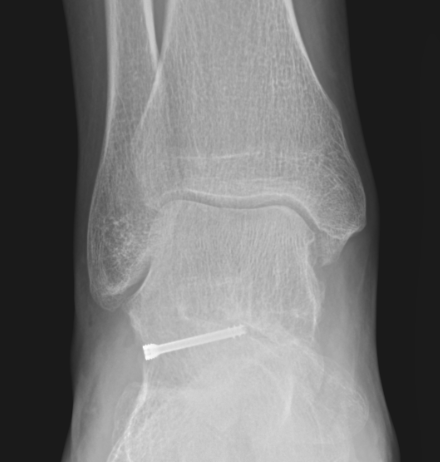

X-ray

Best seen on mortise view

| Non operative | Non operative | ORIF |

ORIF if able Excise fragments to prevent subtalar OA |

Operative Management

Indications

Large / displaced fragments

Intra-articular fracture with risk of subtalar OA

Options

1. ORIF - headless compression screw

2. Excision